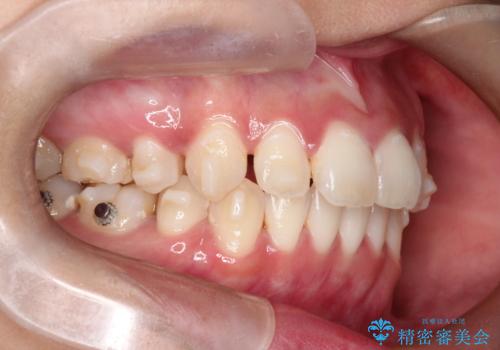

【インビザライン】シザーズバイト、抜歯矯正

- オープンバイトを主訴に来院された患者様です。

抜歯を行うことで、インビザラインを用いて前歯を下げることができ、同時にオープンバイトを改善することができました。

今回はインビザラインのみで治療を終了することができました。